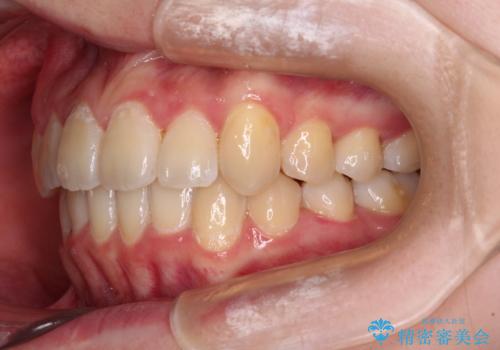

【モニター】八重歯と前歯のクロスバイト ワイヤーを併用しインビザラインで矯正治療

- 前歯のデコボコと八重歯を気にして来院された患者様です。

インビザラインでの治療を希望されていましたが、前歯のクロスバイトや下顎小臼歯の捻転が認められたため、インビザライン単独で治療を行うよりも、ワイヤー装置を併用した方が、治療期間の短縮やトラブル回避できると判断し、ワイヤー装置を併用することとしました。

まずはワイヤー装置により前歯のクロスバイトと下顎小臼歯の捻転を改善し、その後インビザラインにより全体を整える矯正治療を行うこととしました。

前歯のクロスバイトは、インビザラインでの改善中に前歯に過剰な力がかかり、歯髄壊死や歯肉退縮を引き起こすことがあります。また下顎小臼歯は寸胴型のため、捻転を排除することが難しいことが知られています。

それをワイヤー装置にて速やかに改善することで、トータルでの治療期間を短くすることができます。